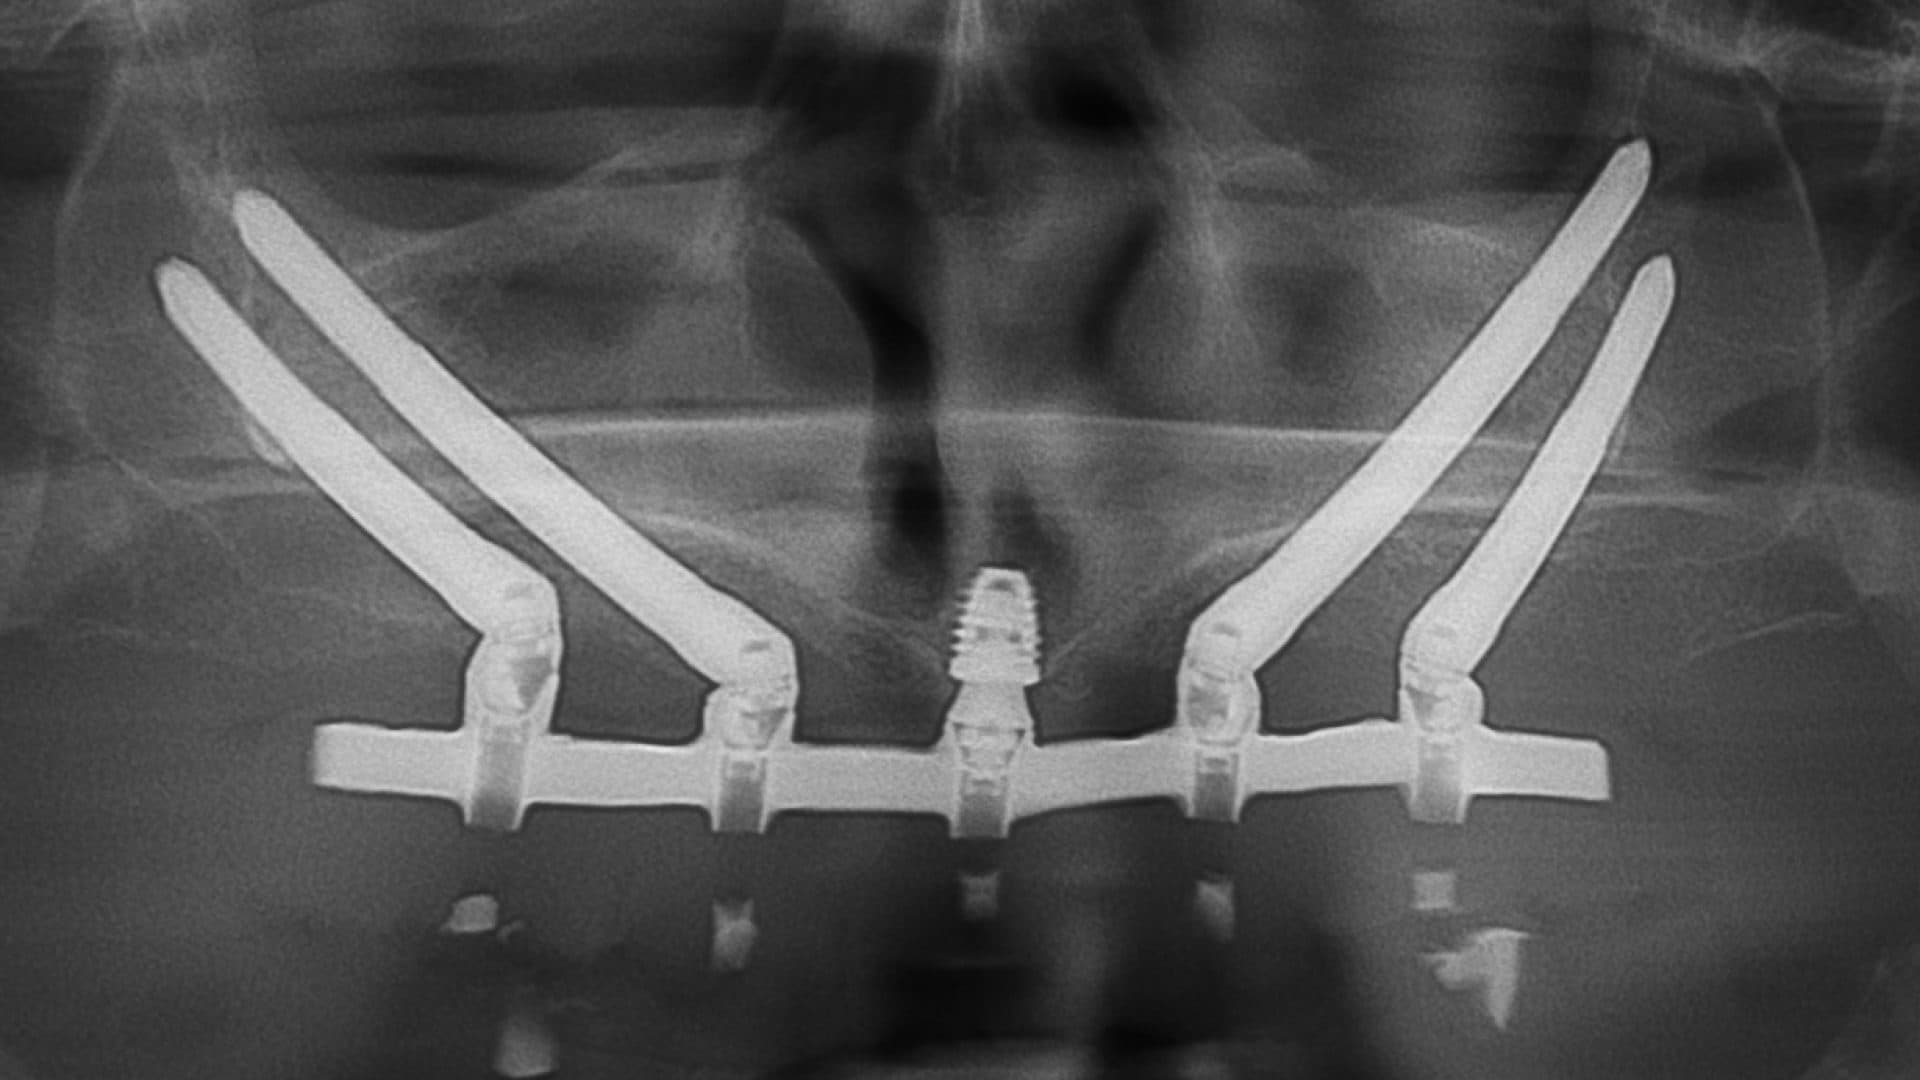

iii. Alignment on x-rays: there should be even spread, rigid connection between the implants, good bone levels, and the height of the prosthesis should be at least as tall as the shortest fixture (See pictures).

Ideal Situation